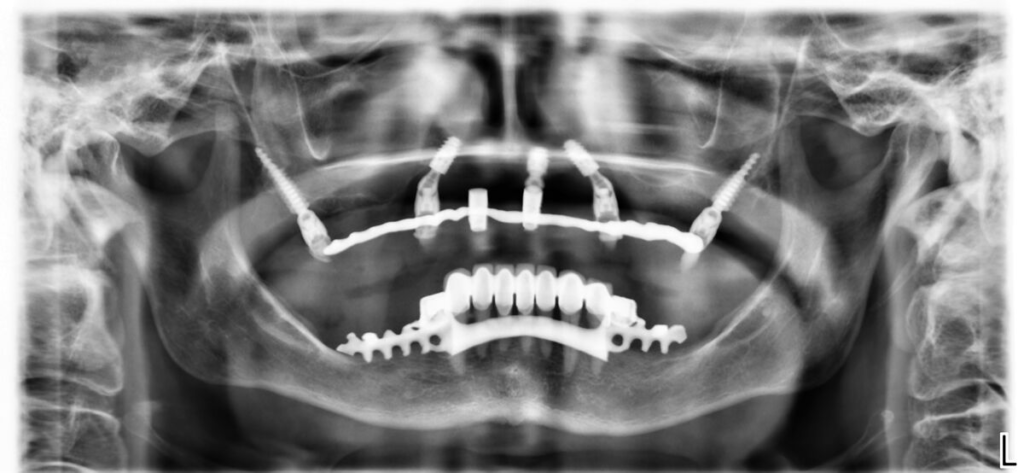

- 4–6 implantátů metodou All-on-X

Po 4–6 měsících nasazujeme trvalý můstek.

Používáme multivrstvý zirkon pro maximální estetiku, pevnost a dlouhou životnost.

Technika All-on-X — II. fáze